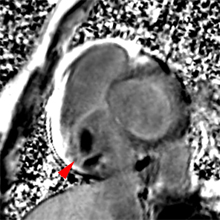

– Insuffisance aortique : recherche de bicuspidie et quantification de la fraction de régurgitation par l’IRM sont fiables.

– Rétrécissement aortique : Recherche de bicuspidie fiable, possibilité de quantification de la surface valvulaire et du gradient systolique.

– Les abcès annulaires infectieux ou froids calcifiés constituent de bonnes indications pour l’IRM cardiaque.